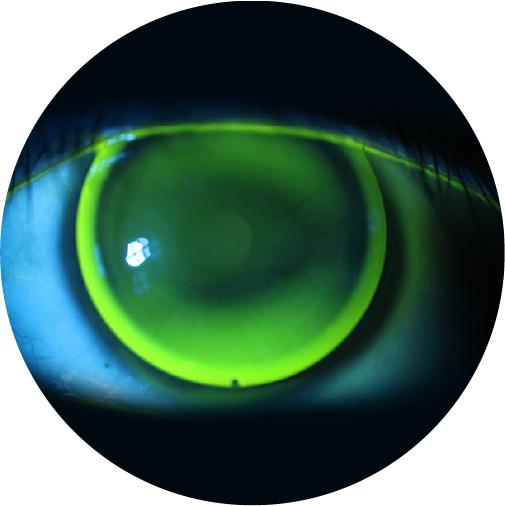

Descubre los lentes rígidos personalizados, diseñados especialmente para corregir queratocono, astigmatismo elevado y otras irregularidades corneales. Claridad visual real, hecha a tu medida.

Diseñados por mapeo 3D exclusivamente para tu ojo

Visión clara incluso en casos complejos de queratocono

Utilizamos diseño asistido por computadora, que combina la información de topografía corneal, y la inteligencia artificial con algoritmos avanzados de modelado 3D para crear lentes que se adapten perfectamente a la forma única de tus ojos.